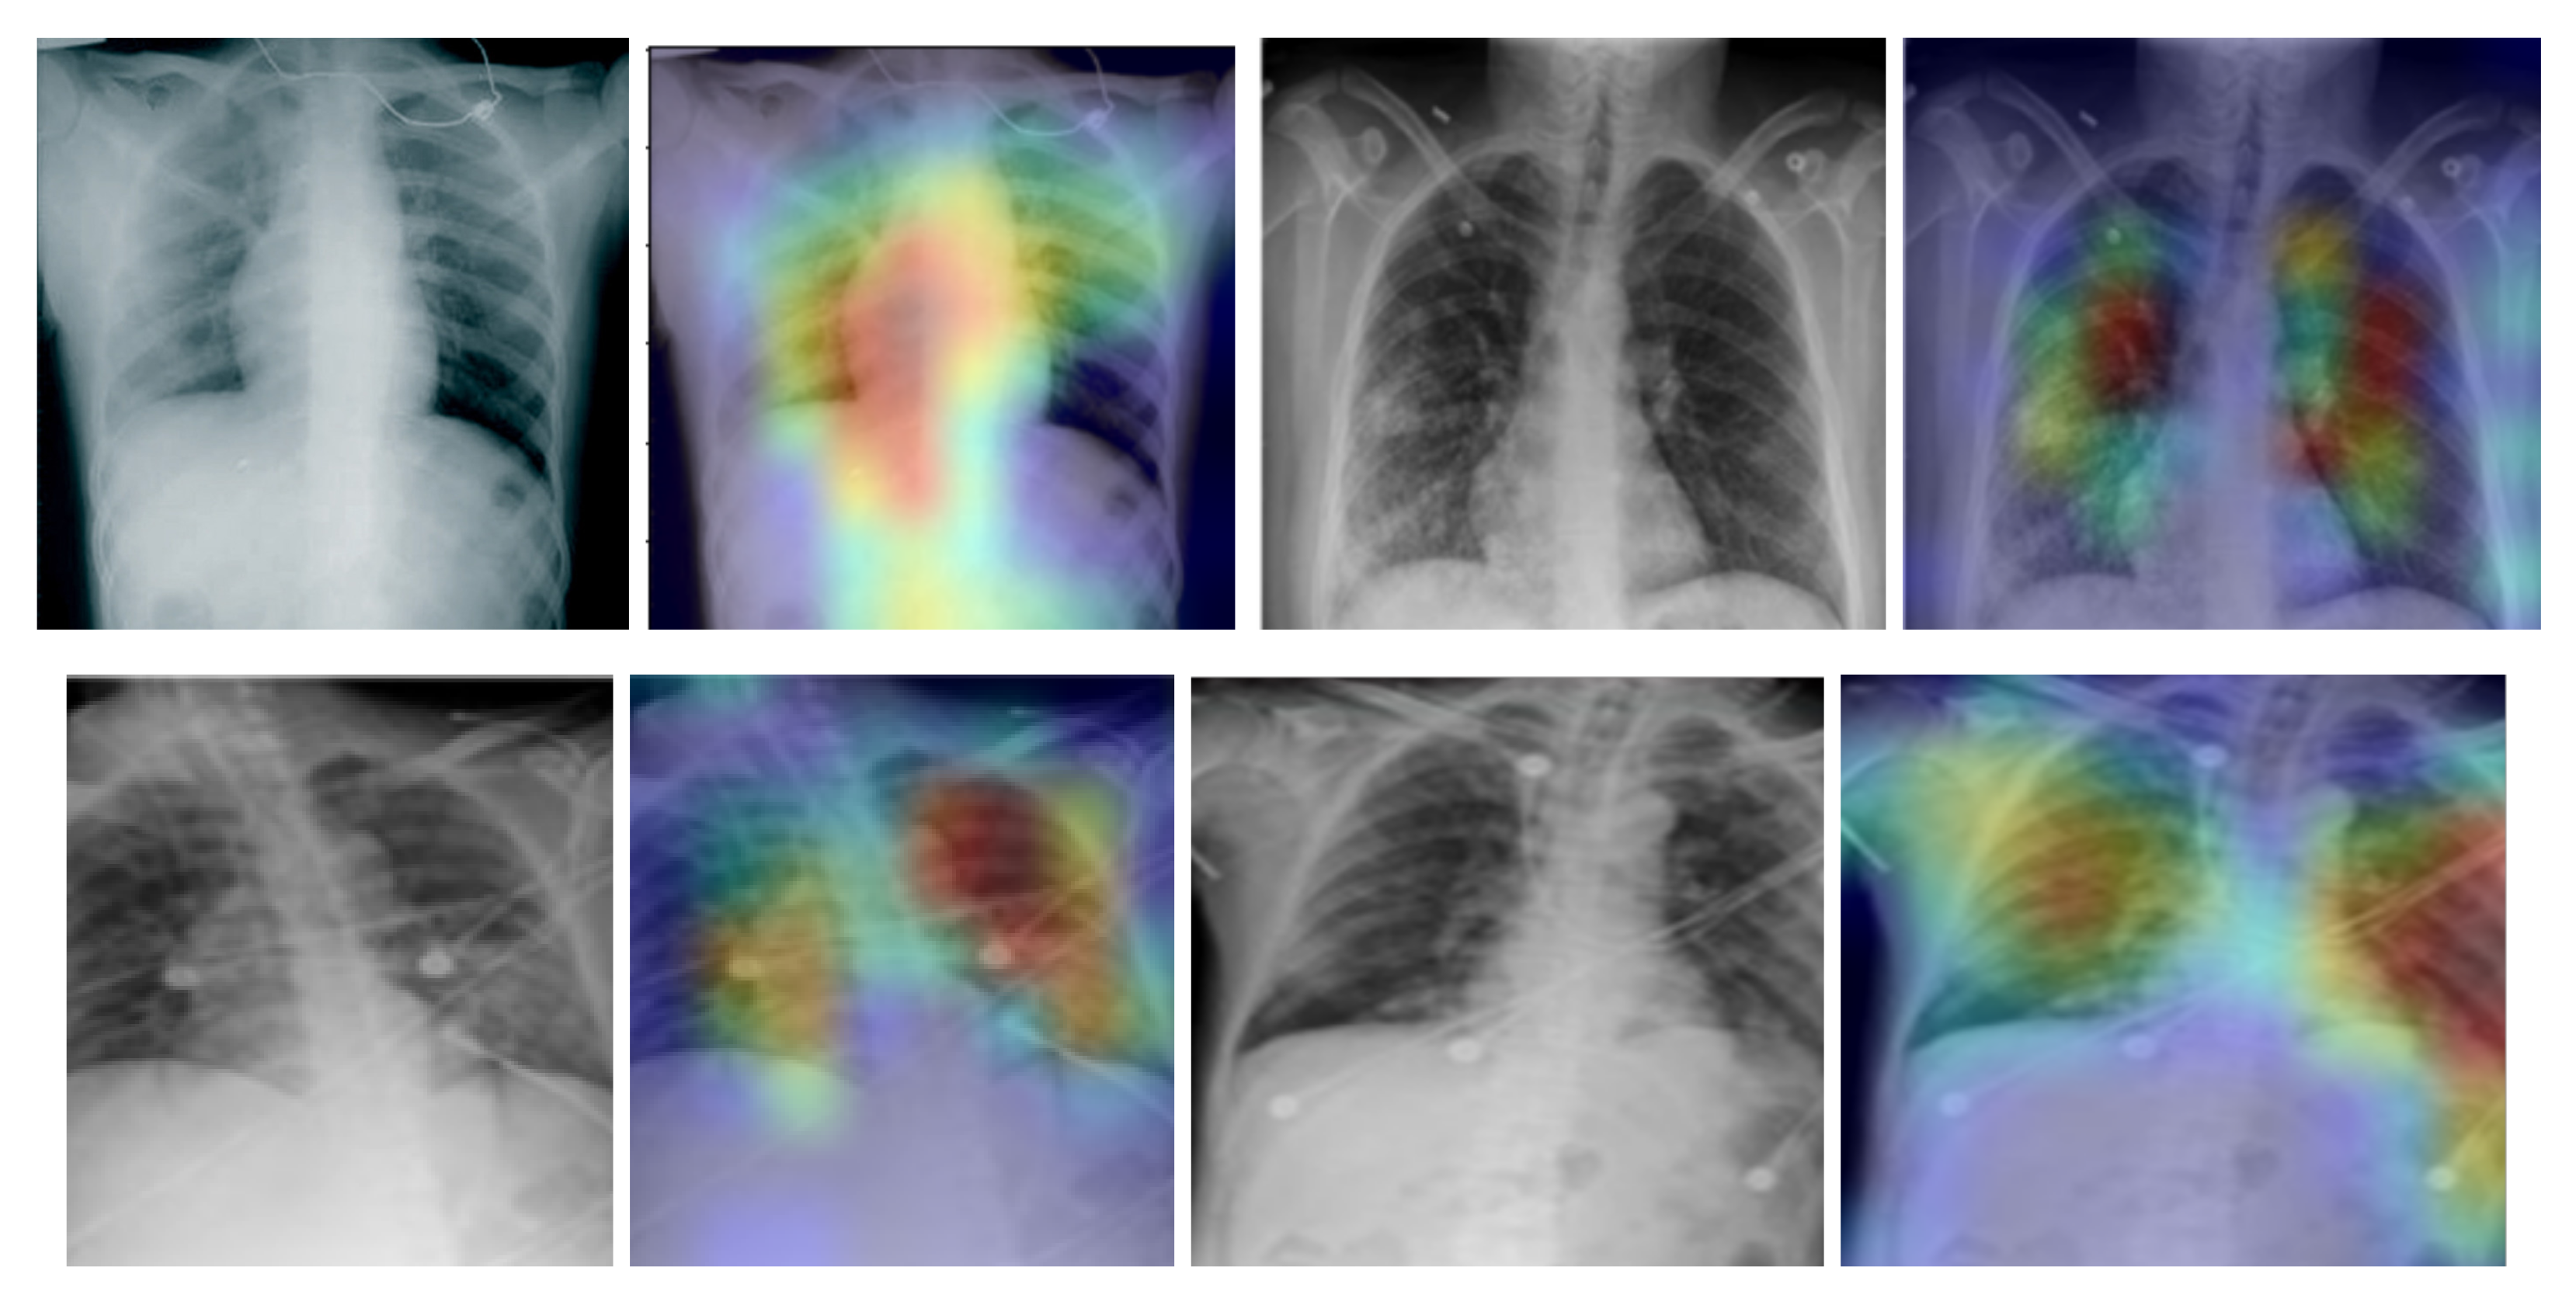

In addition, we used the gradient-weighted class activation mapping (Grad-CAM) method to visualise class activation heat maps for the best-performing model (EfficientNetB4-based Approach 1), as shown in Figure 5 for four COVID-19-positive images. The Grad-CAM method uses the gradients of any target class in a classification network flowing into the final convolutional layer to produce a coarse localisation map that highlights the most important image regions for predicting the specific class. It is based on the CAM method, which finds the discriminative regions for a CNN prediction through the computation of class activation maps, which assign importance to every position in the last convolutional layer by computing the linear combination of the activations, weighted by the corresponding output weights for the observed class. Grad-CAM extends the CAM method by incorporating gradient information in the computation of the class activation maps (heat maps). By using the heat maps from the Grad-CAM method, we can examine the regions within the input image on which the CNN model focuses to make the decision for each class. By examining the examples in Figure 5 for our best-performing model, it is evident that the trained CNN model focuses on the areas of the lungs, as expected, and thus, we can be confident that the model relies on features extracted from the image regions that contain the information regarding COVID-19, viral pneumonia or healthy lungs, and not on information related to the images, to artefacts in the images or to the source of the images.

Figure 5.

Grad-CAM visualisation for the COVID-19 class using the EfficientNetB4-based Approach 1 model for four chest X-ray images.